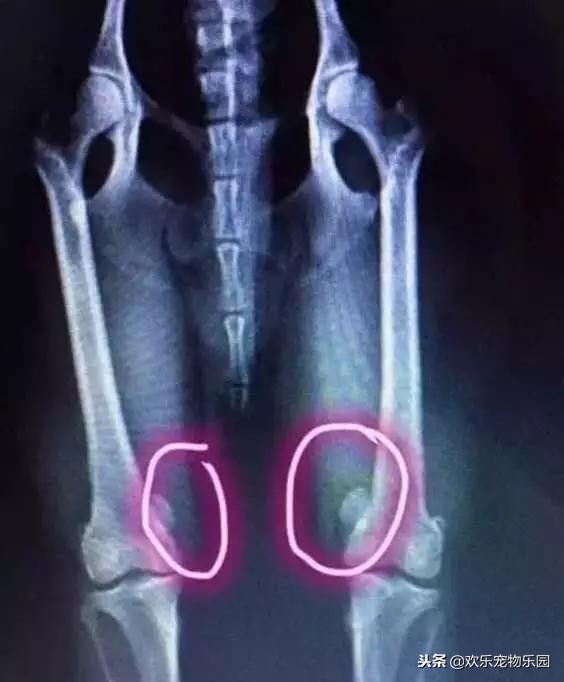

但是,你知道那条在2016年曾登上电视,并荣获无数荣誉的狗狗,现在是什么样的状况吗?由于那条泰迪长期直立行走,已经导致狗狗的后腿髌骨移位,严重影响了狗狗日常生活,而且最终只能通过手术进行修正与恢复。

而关于狗狗的四肢,我们必须要明白一个关于狗狗生理机能的科普知识。那就是狗狗的四肢中,前腿所承受的身体重量比例占到了70%,而后退则占到了30%。那么试想一下,如果狗狗直立行走,本该由前腿承担的重量,一下子全部转移到了后退上,会是什么样的后果?

毋庸置疑,这当然会让狗狗四肢出现严重损耗,长期以往的话,狗狗的后腿很容易出现错位、发炎等情况。如果主人发现了这些问题,还不及时改正的话,那么狠有可能让狗狗直接瘫痪。